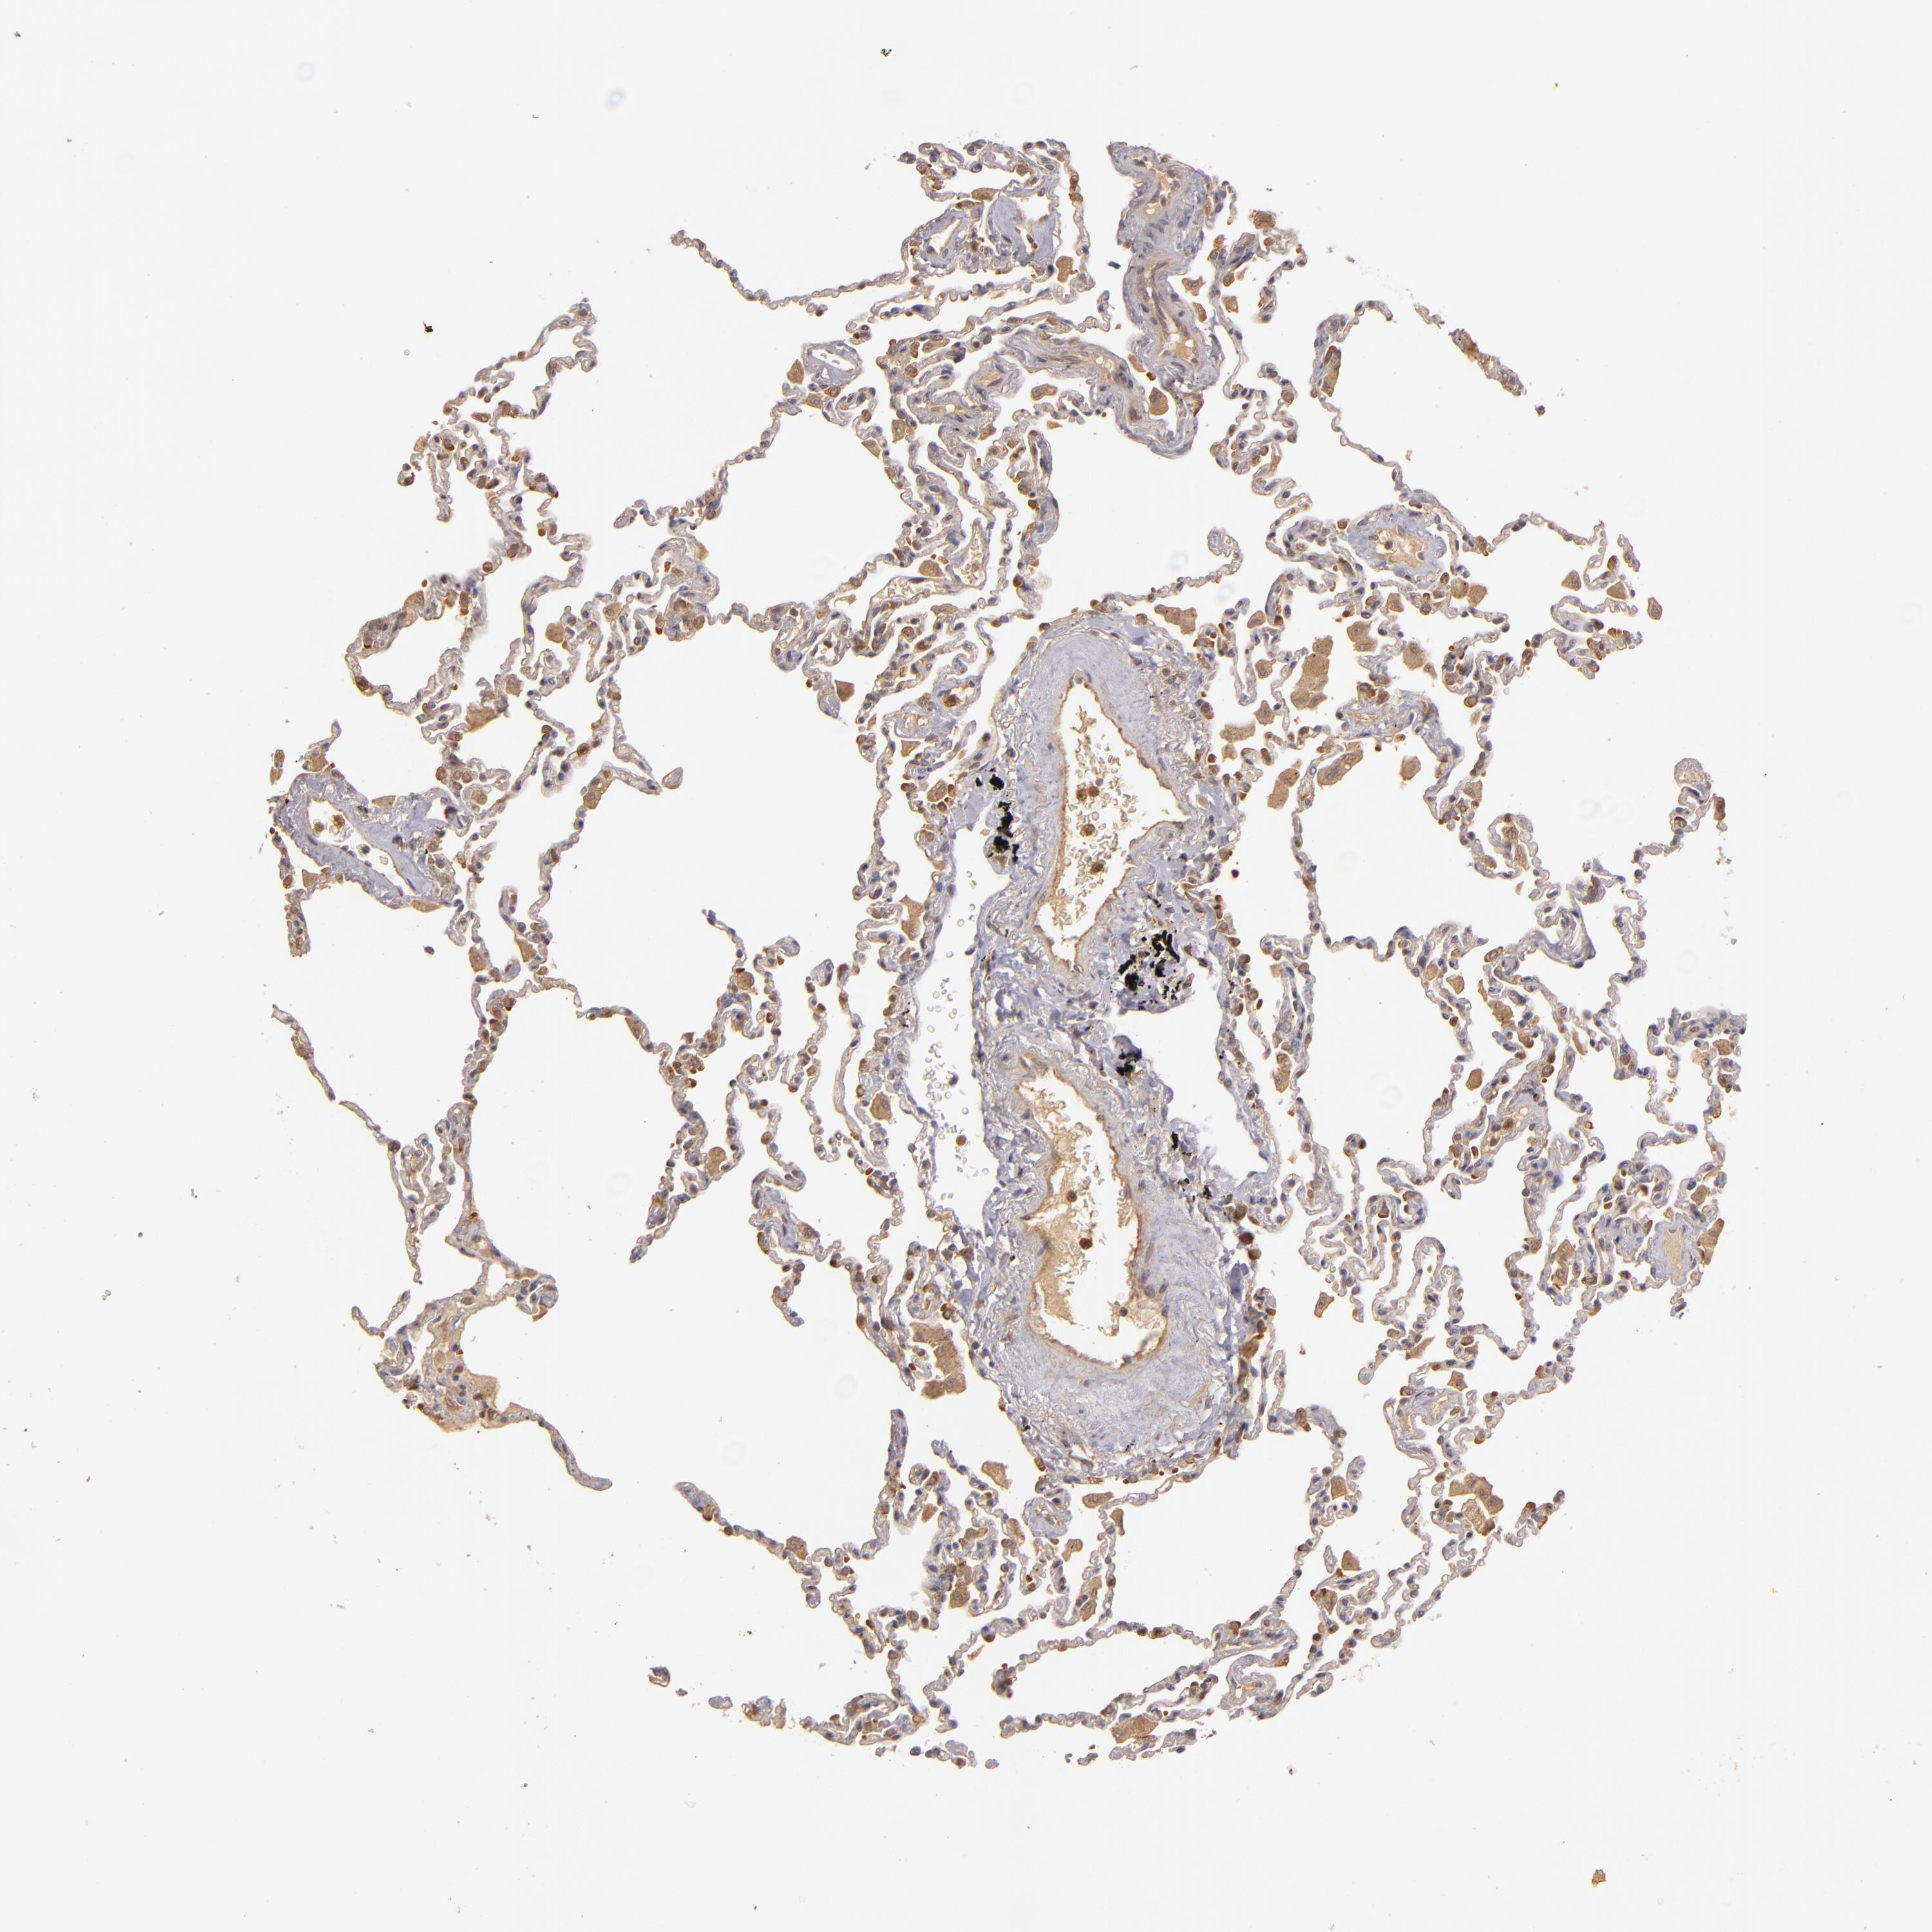

LUNG - Antibody stainingi

Antibody staining in the annotated cell types in the current human tissue is reported as not detected, low, medium, or high, based on conventional immunohistochemistry profiling in selected tissues. This score is based on the combination of the staining intensity and fraction of stained cells. Each image is clickable and will lead to virtual microscopy that enables deeper exploration of all samples and also displays staining intensity scores, fraction scores and subcellular localization as well as patient and tissue information for each sample.

Antibody HPA001863Antibody HPA001890Antibody CAB010469Antibody CAB013225

Alveolar cells HighMediumLow-

Alveolar cells type I ---Medium

Alveolar cells type II ---Medium

Endothelial cells ---Not detected

Macrophages HighHighHighHigh